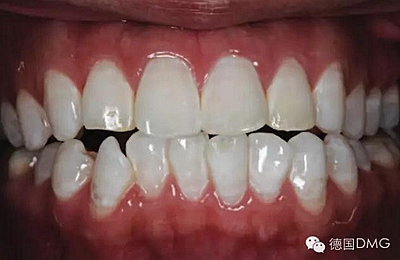

一28歲女性患者來我院修復(fù)科就診,主訴為前牙嚴(yán)重的牙齒著色和缺損十余年,要求改善牙齒的美觀。臨床檢查表明該患者有重度氟斑牙,極大的影響了前牙美學(xué)。

考慮到患者為年輕人,保守治療方法比傳統(tǒng)侵入性治療手段更為合適。術(shù)前牙周治療預(yù)防牙齦炎癥和改善牙齦健康狀態(tài),隨后聯(lián)合采用釉質(zhì)打磨、牙漂白和樹脂滲透來處理牙釉質(zhì)表面。

5、由于氟斑牙存在釉質(zhì)礦化不全等問題,家庭漂白兩周后,使用標(biāo)準(zhǔn)的樹脂滲透技術(shù) (Icon, DMG Products, Hamburg. Germany) 來預(yù)防釉質(zhì)齲。最后,徹底改變患者的前牙美學(xué),并在一年后仍保持穩(wěn)定。

利用釉質(zhì)打磨技術(shù)聯(lián)合牙齒漂白和樹脂滲透技術(shù)的微創(chuàng)方法是治療重度氟斑牙的有效方式。同時(shí),這一技術(shù)費(fèi)用低、省時(shí)間。